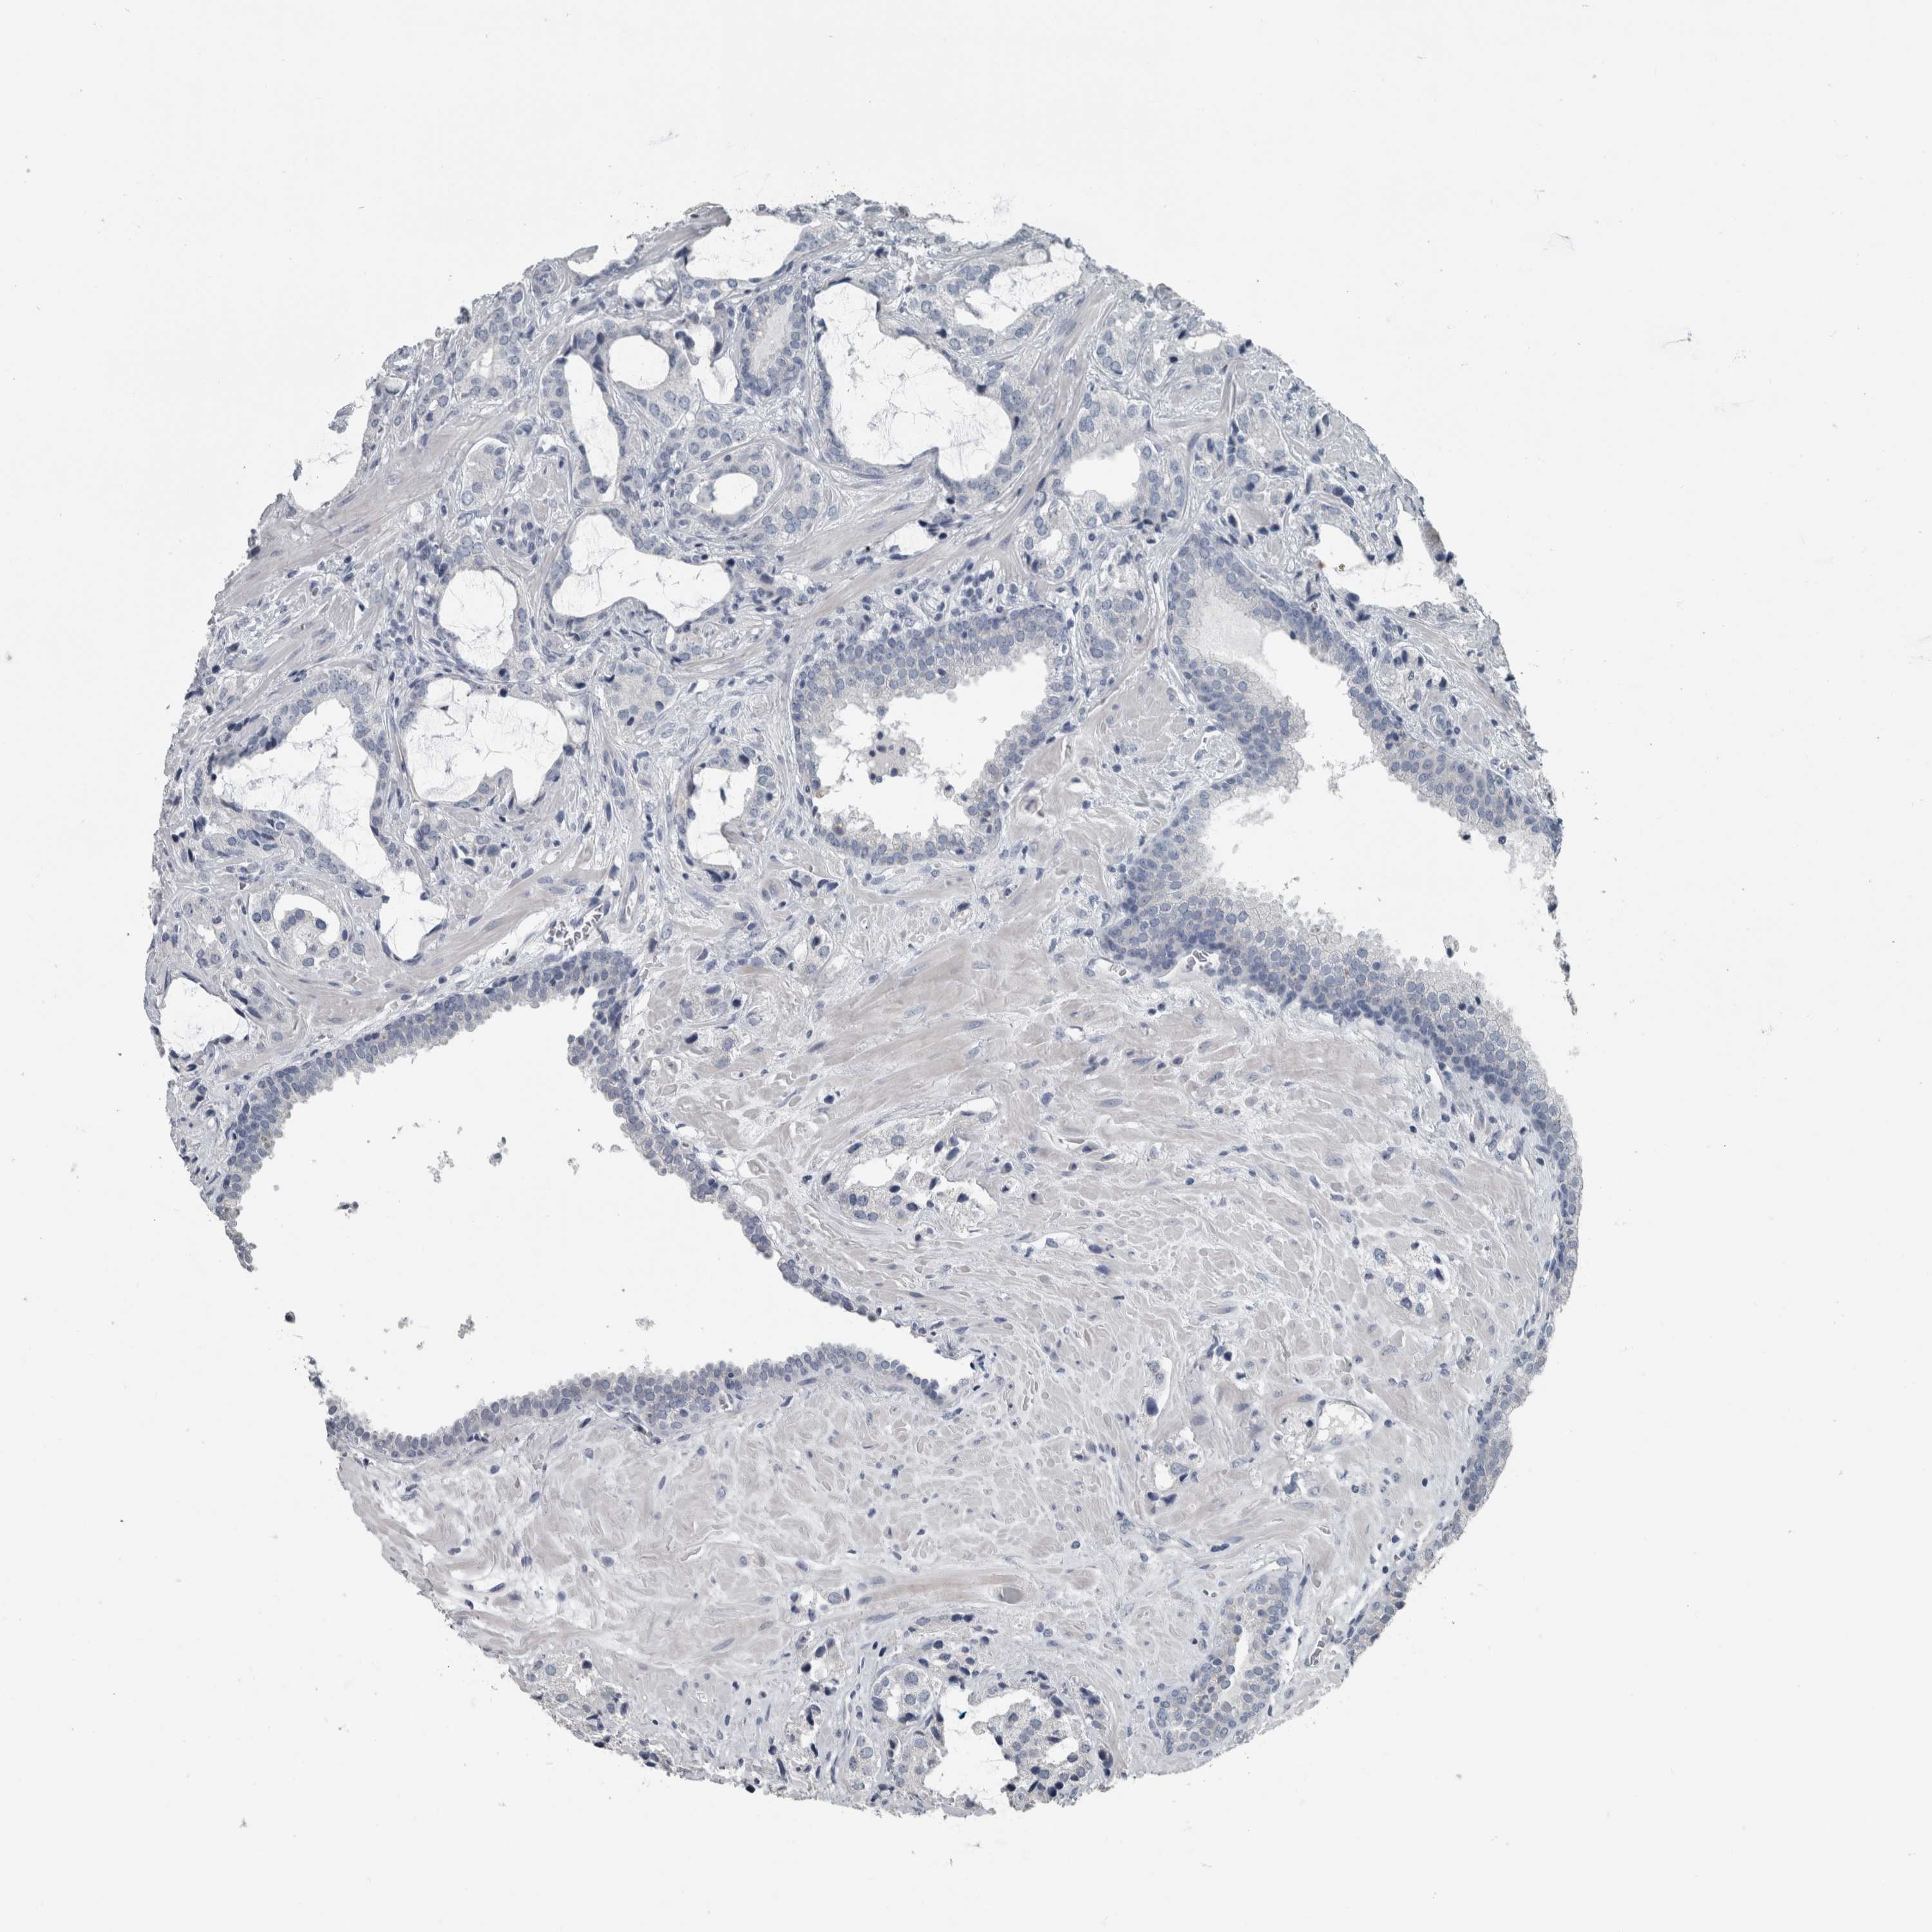

PROSTATE CANCER - Protein expressioni

A mouse-over function shows sample information and annotation data. Click on an image to view it in a full screen mode. Samples can be filtered based on level of antibody staining by selecting one or several of the following categories: high, medium, low and not detected. The assay and annotation is described here.

Note that samples used for immunohistochemistry by the Human Protein Atlas do not correspond to samples in the TCGA dataset.

Antibody stainingi

Antibody staining in the annotated cell types in the current human tissue is reported as not detected, low, medium, or high, based on conventional immunohistochemistry profiling in selected tissues. This score is based on the combination of the staining intensity and fraction of stained cells.

Each image is clickable and will lead to virtual microscopy that enables deeper exploration of all samples and also displays staining intensity scores, fraction scores and subcellular localization as well as patient and tissue information for each sample.

Antibody HPA027236

Staining

High

Medium

Low

Not detected

Intensity

Strong

Moderate

Weak

Negative

Quantity

>75%

75%-25%

<25%

None

Location

Nuclear

Cytoplasmic/membranous

Cytoplasmic/membranous,nuclear

Adenocarcinoma, High grade

Adenocarcinoma, Low grade

Adenocarcinoma, Medium grade